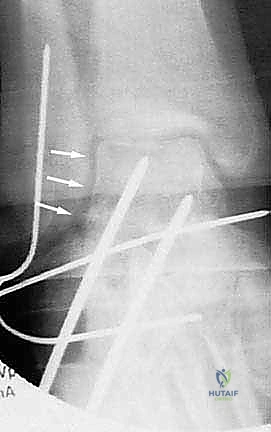

Page 40 of 47Thumb Carpometacarpal Joint Arthroplasty: An Intraoperative Masterclass in Resurfacing and Total Joint Replacement

- Mastering Silicone Arthroplasty for MCP and PIP Joints: An Intraoperative Guide

- Thumb Carpometacarpal Joint Ligament Stabilization: An Operative Masterclass

- Mastering Thumb CMC Resection Arthroplasty with FCR Suspensionplasty